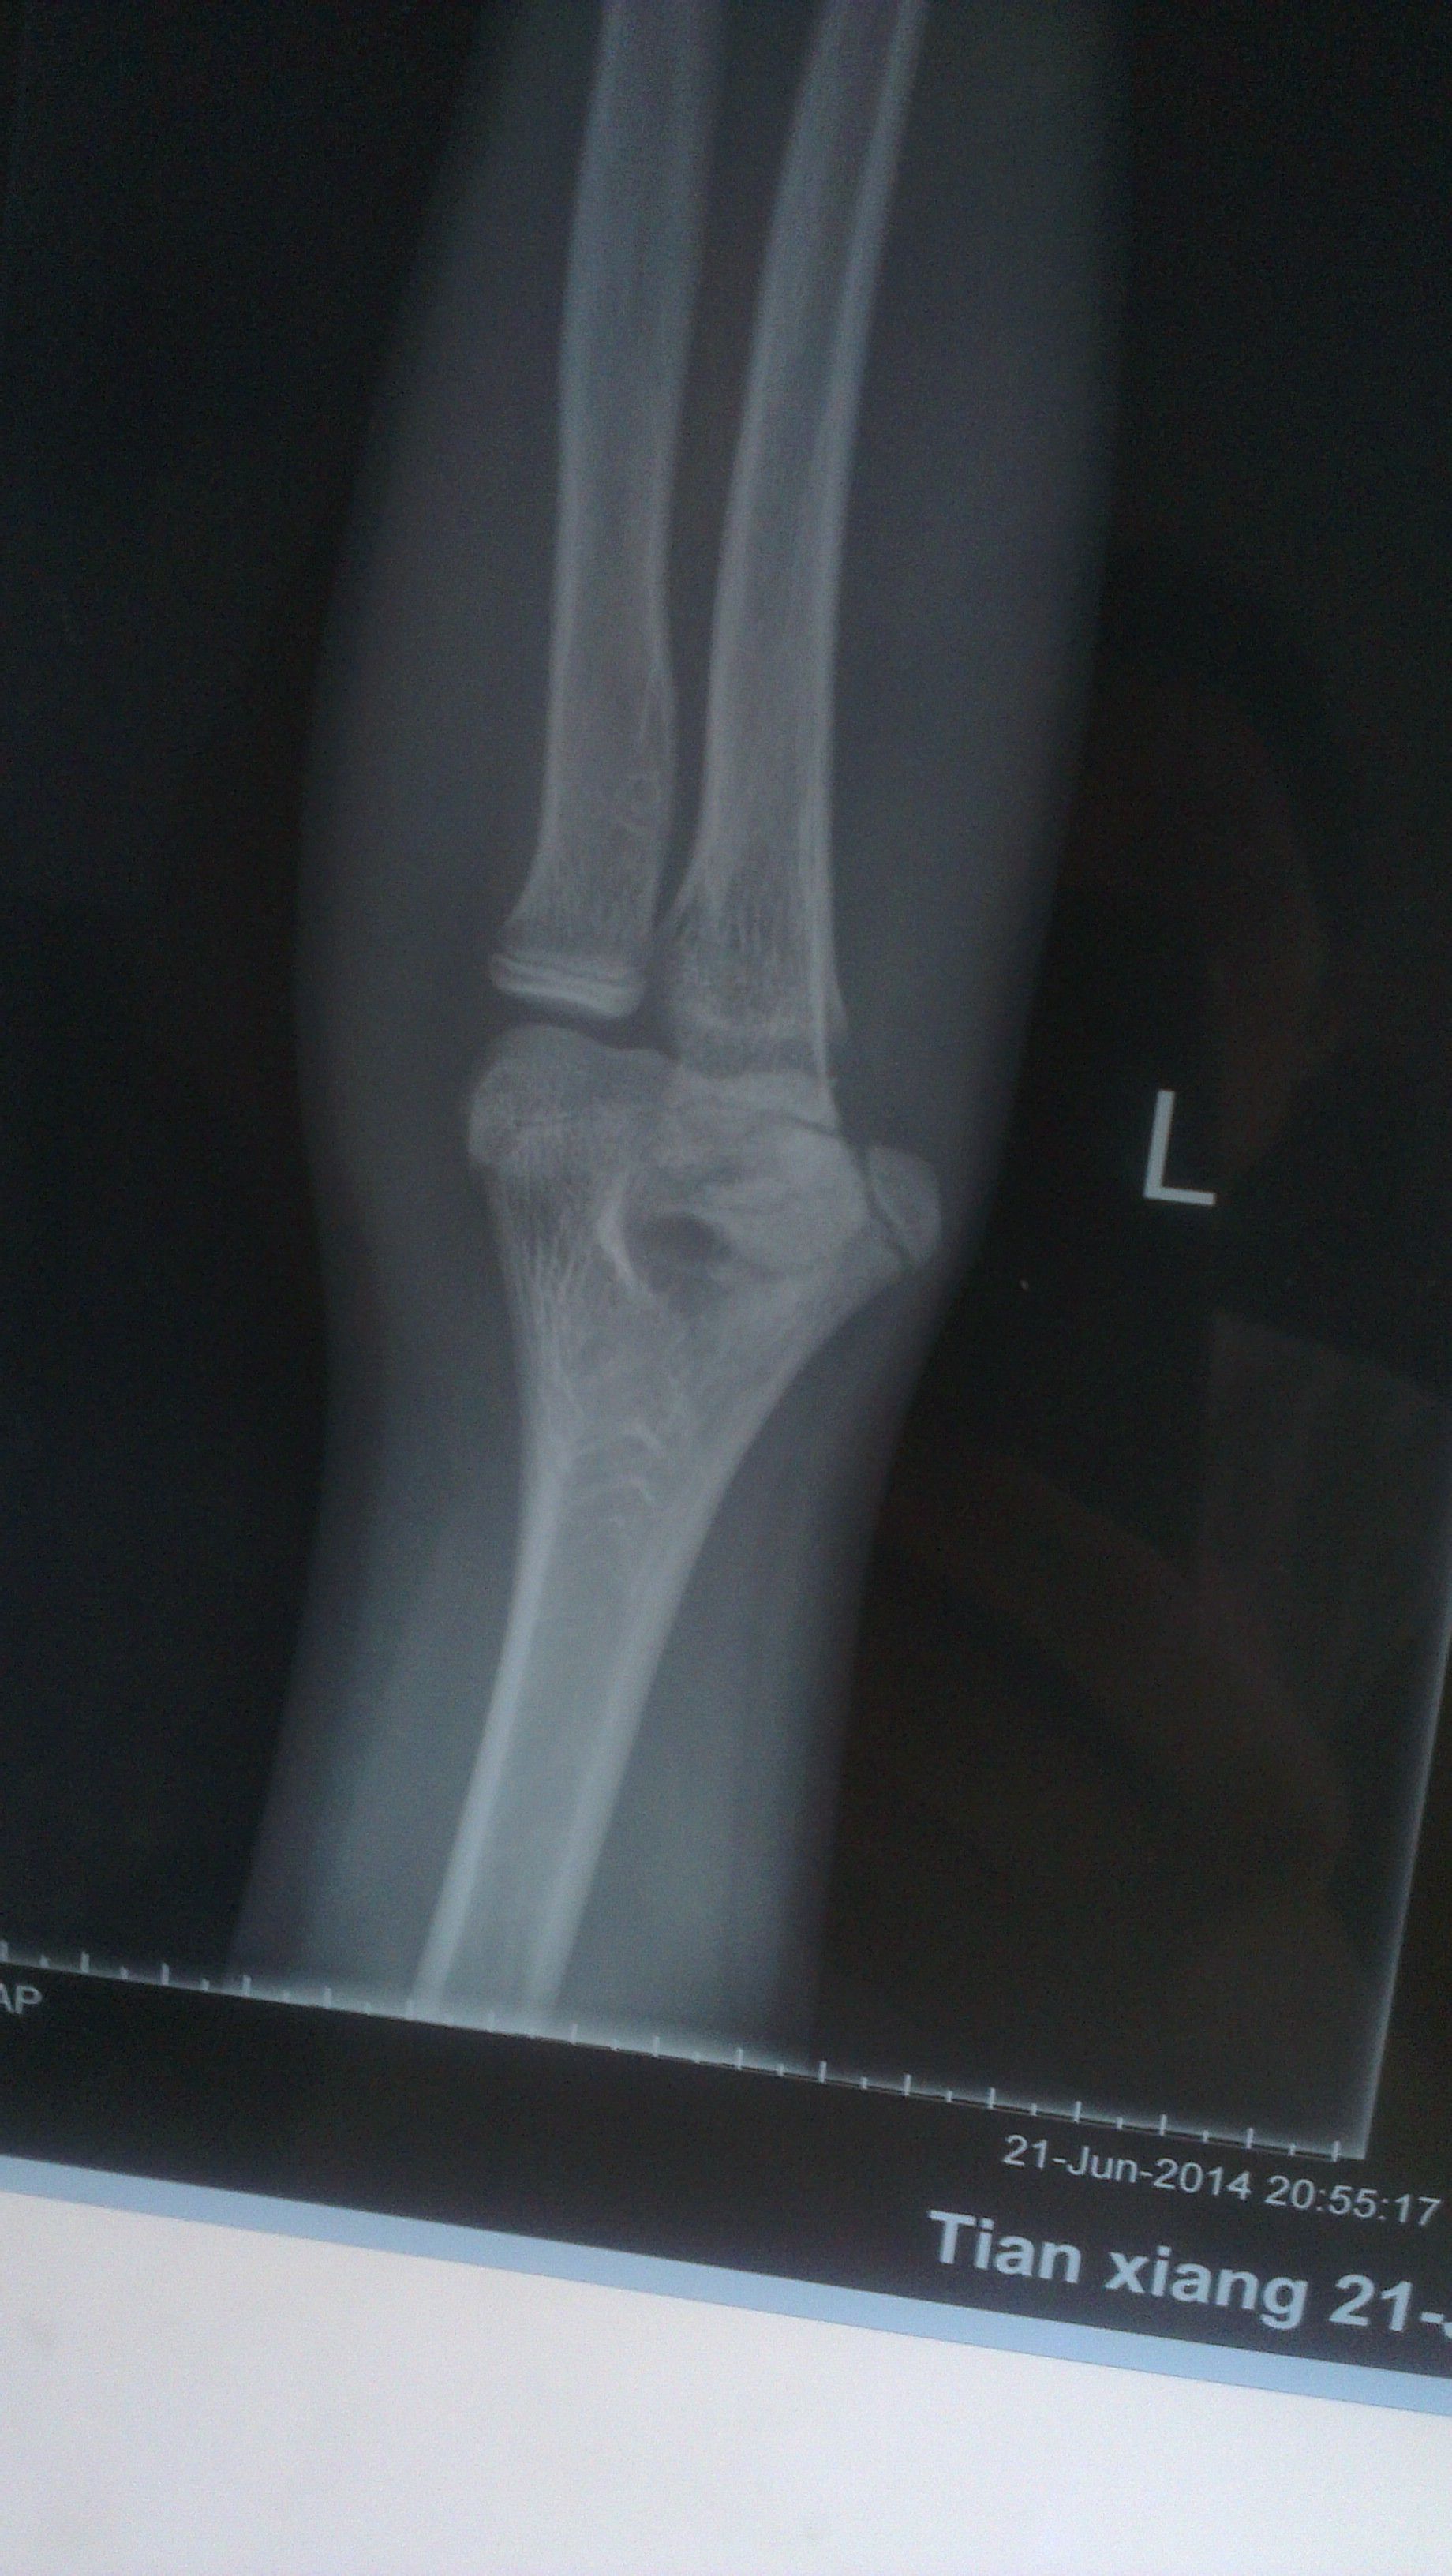

14岁小孩打篮球左肘关节负伤了 14岁小孩打篮球左肘关节负伤了,下面是片子,请专业医生诊断下:1,是什么问题?2,怎么治疗?有什么风险 点击展开 匿名用户 2014-06-27 12:49 为您推荐: 其他回答 你好,这个是要让医生给伤点药物的呢,还有就是要自己注意给宝宝好好的护理的呢,希望早日康复 可靠的悠闲80 2014-06-29 08:34 相关问题 四岁小孩肘关节骨折能保守治疗吗 你好!我小孩现14岁了他特喜欢打篮球 大家都说他可以进体校但是我又不知道哪里有啊我是重庆人 知不知道 有一个美国电影 一13岁小孩 在NBA 和大人们打篮球 这电影叫什么呀?